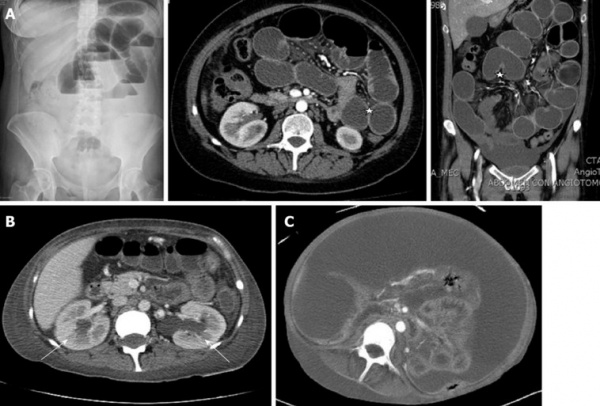

а - псевдообструкция. Растяжение тонкой и толстой кишок (обзорная рентгенограмма)

б-в - арактерное сильное расширение двенадцатиперстной кишки и дистальной части тонкой кишки у двух пациентов с гистологическим подтвержденным диагнозом висцеральной миопатии:

б — пассаж бария; в — компьютерная томограмма (двенадцатиперстная кишка лежит позади желудка около центра изображения).